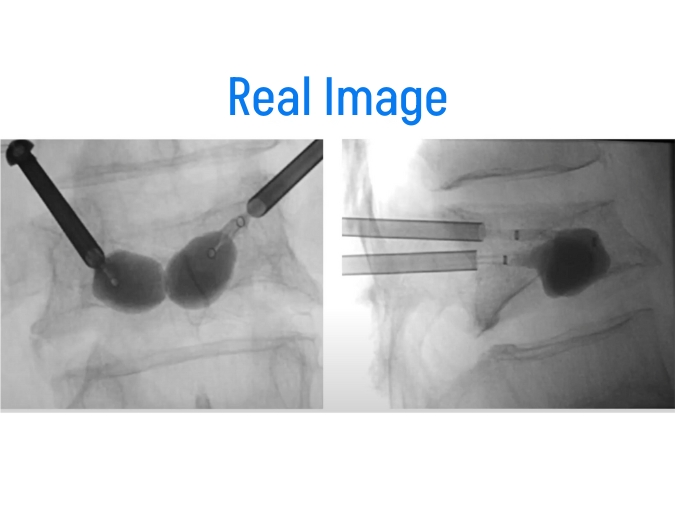

Vertebroplasty and kyphoplasty are both minimally invasive procedures performed under fluoroscopic guidance to treat vertebral compression fractures. These fractures typically occur in the thoracic (mid-back) or lumbar (lower back) regions of the spine and can cause severe pain and disability. Both procedures involve the injection of bone cement into the fractured vertebra to stabilize the fracture and alleviate pain. While similar in principle, there are some differences between vertebroplasty and kyphoplasty in terms of technique and outcomes.

– Kyphoplasty involves the use of a balloon-like device to create a cavity within the fractured vertebra before injecting the bone cement.

– The balloon is inflated to restore the height of the collapsed vertebra and create space for the cement.

– Once the cavity is created, the bone cement is injected, stabilizing the fracture and reducing spinal deformity.

- Procedure: The procedure is performed by an interventional radiologist or spine surgeon. Using fluoroscopic guidance, a small incision is made in the skin, and a needle is advanced into the fractured vertebra. In vertebroplasty, bone cement is injected directly into the vertebra. In kyphoplasty, the balloon is inserted and inflated to create a cavity before injecting the cement.